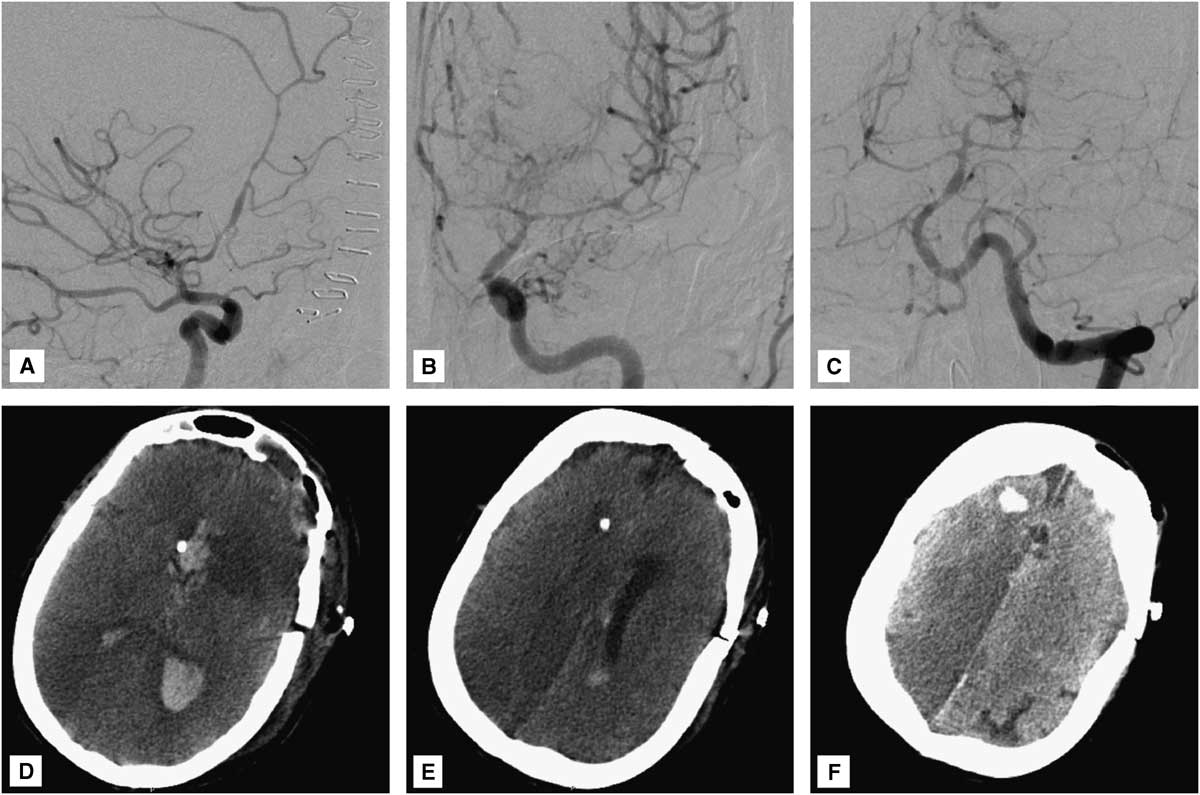

Postoperatively, the patient’s neurological condition was unchanged from baseline, with persistence of a symmetric motor examination (withdrawal of all four extremities to pain). Head CT revealed an expected small infarct in the head of the left caudate nucleus, without involvement of the internal capsule (Figure 1H,I). Unfortunately, 3 days later (SAH day 6), the patient developed severe diffuse cerebral vasospasm (Figure 4A-C) with marked neurological deterioration to a Glasgow coma score of 3T. Despite maximal medical treatment (triple H therapy) and intra-arterial verapamil infusion, she developed extensive bihemispheric infarctions (Figure 4D-F). Given her poor baseline and current neurological condition, and the severity and refractoriness of her vasospasm, the family requested to withdraw medical care, and the patient ultimately died.

Figure 4 (A) Right internal carotid, (B) left internal carotid, and (C) left vertebral angiograms demonstrate severe diffuse (proximal and distal) vasospasm involving the bilateral anterior cerebral arteries, left middle cerebral artery, and vertebrobasilar circulation. (D-F) Head CT reveals multiple bihemispheric infarctions secondary to vasospasm. Video: Microsurgical clipping of a dissecting aneurysm of the left recurrent artery of Heubner.